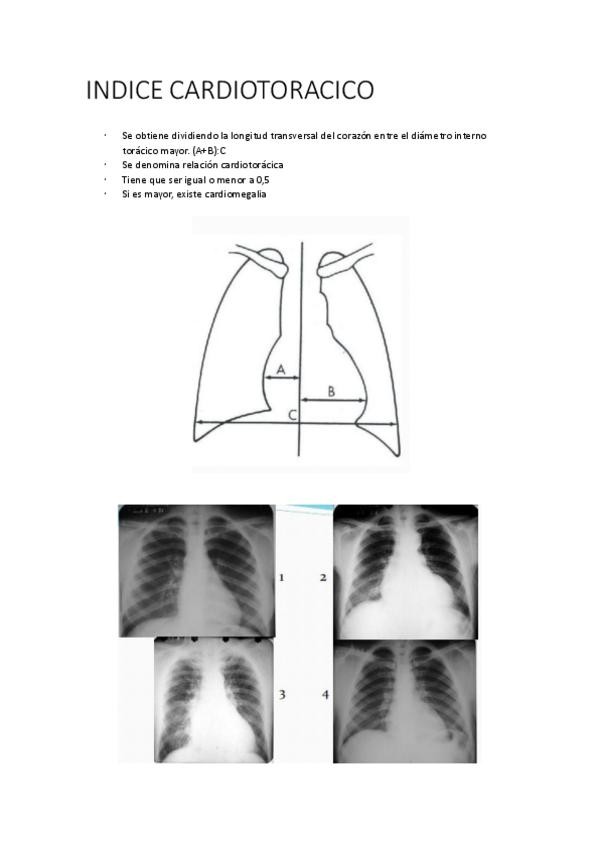

He publicado nuevos apuntes de 3º Cuidados al Paciente Crónico y Terminal: Apuntes-INDICE-CARDIOTORACICO.pdf

1 página